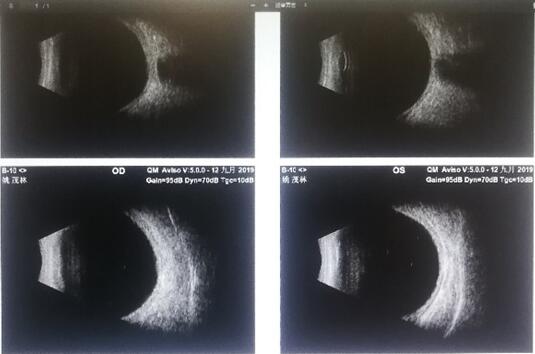

病人术后复查

术后视力0.8,姚老师收获好视力

果不其然,正如胡院长所言,姚老师术后第一天就可以清楚的视物,眼睛也不痛了。

“关键还是胡院长医术高明,医德好,为病人想的全面,经验丰富,才能有现在的理想效果,感谢你们东区爱尔眼科医院,特别感谢胡院长,救了我的眼睛,让我还可以在我热爱的讲台上实现桃李芬芳梦!”姚老师感慨。